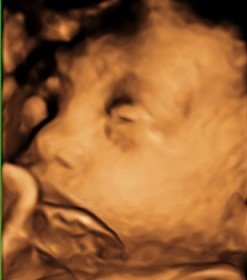

36 WEEKS

Beautiful close-up!

3D ultrasound of baby

Lifelike image of unborn baby!

Flesh tone 3D ultrasound

Fetal profile